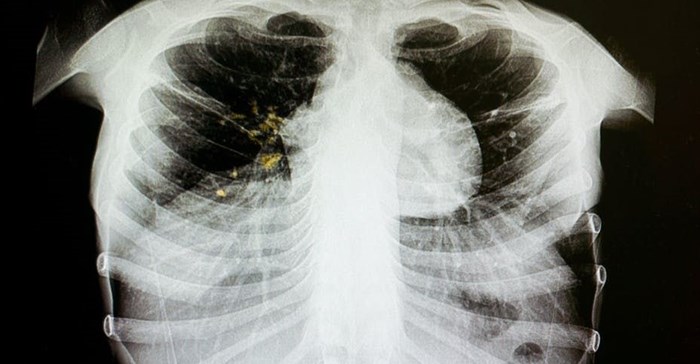

The standard first-line treatment regimen used for newly diagnosed TB patients involves taking four different drugs over a period of six months. Some patients experience varying degrees of adverse reactions as a result. These factors have led to patients defaulting on their treatment. This, in turn, has led to a rise in drug resistance.

TB drug resistance – when the bacteria become resistant to at least one anti-TB drug – is a growing problem across the world. Current treatments that include more than one drug known as combination therapy have become inadequate because the bacteria have devised ways to survive even when antibiotics are used. An estimated 3.5% of new cases and 18% of previously treated cases of TB are drug resistant. There is therefore still a need to identify alternative drugs. But the drug discovery process is fairly lengthy (10 to 15 years). This timeline can be shortened with the aid of computers.